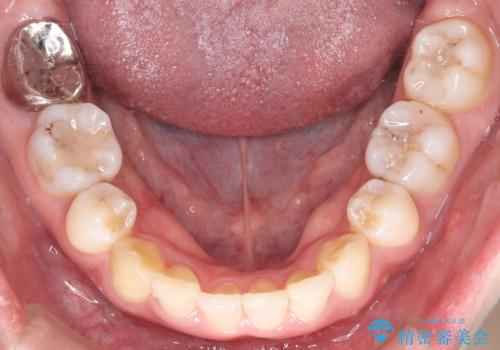

- 前歯から奥歯にかけて歯の重なりが激しい歯のがたつき(重度叢生)を主訴にご来院されました。精密検査の結果、歯が並ぶスペースが大幅に不足しており、歯並びを整え、口元を美しく引っ込めるためには、スペースの確保が必要と診断しました。そこで、上下左右の第一小臼歯(4番目の歯)を計4本抜歯し、そのスペースを利用して歯並び全体を整える抜歯矯正の治療計画を立案。装置には、透明で目立たないインビザラインを採用し、審美性と治療効果の両立を目指しました。

今回の治療では、重度の叢生を改善するため、まず計画通り上下左右4本の小臼歯を抜歯し、歯を並べるための十分なスペースを確保しました。装置には透明で取り外し可能なインビザラインを使用。抜歯によってできたスペースを最大限に活用し、マウスピースを定期的に交換しながら、デコボコを解消しつつ、前歯を効果的に後退させました。

治療の結果、長年の悩みであった重度の歯のがたつきが解消され、口元の突出感も改善。機能的にも安定し、審美的にも美しい、理想的な歯並びを獲得していただけました。